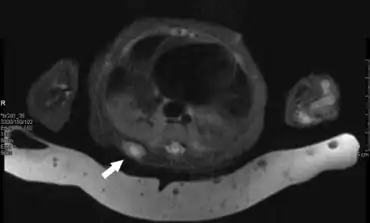

IMF tumors are usually painless, well-encapsulated, rubbery to hard, and freely movable-to-fixed masses.[7] They may be evident at birth in up to 60% of cases[3] but generally go undetected until they [8]are diagnosed in the first year of life,[7] uncommonly in older infants and young (<10 years/old) children,[3] or rarely in older children and adults (one individual was diagnosed with IMF at 85 years of age).[9] The tumors may be flesh-colored papules or nodules; plaques (i.e. flat-topped papules that are equal to or greater than 10 mm in largest diameter); pedunculated, calcified masses; or ulcerated, necrotic masses.[3] Most of these tumors are <1 cm in diameter[3] but can be much larger, e.g. 5.2 cm in diameter.[1] At least 9 IMF cases described in the English literature were diagnosed in fetuses based on the findings of fetal spectrogram and/or magnetic resonance imaging.[6][10] IMF tumors in the viscera or deep tissues may present with serious or life-threatening signs and symptoms of organ and/or deep tissue damage due to these tumors space-filling and pressuring effects.[8]